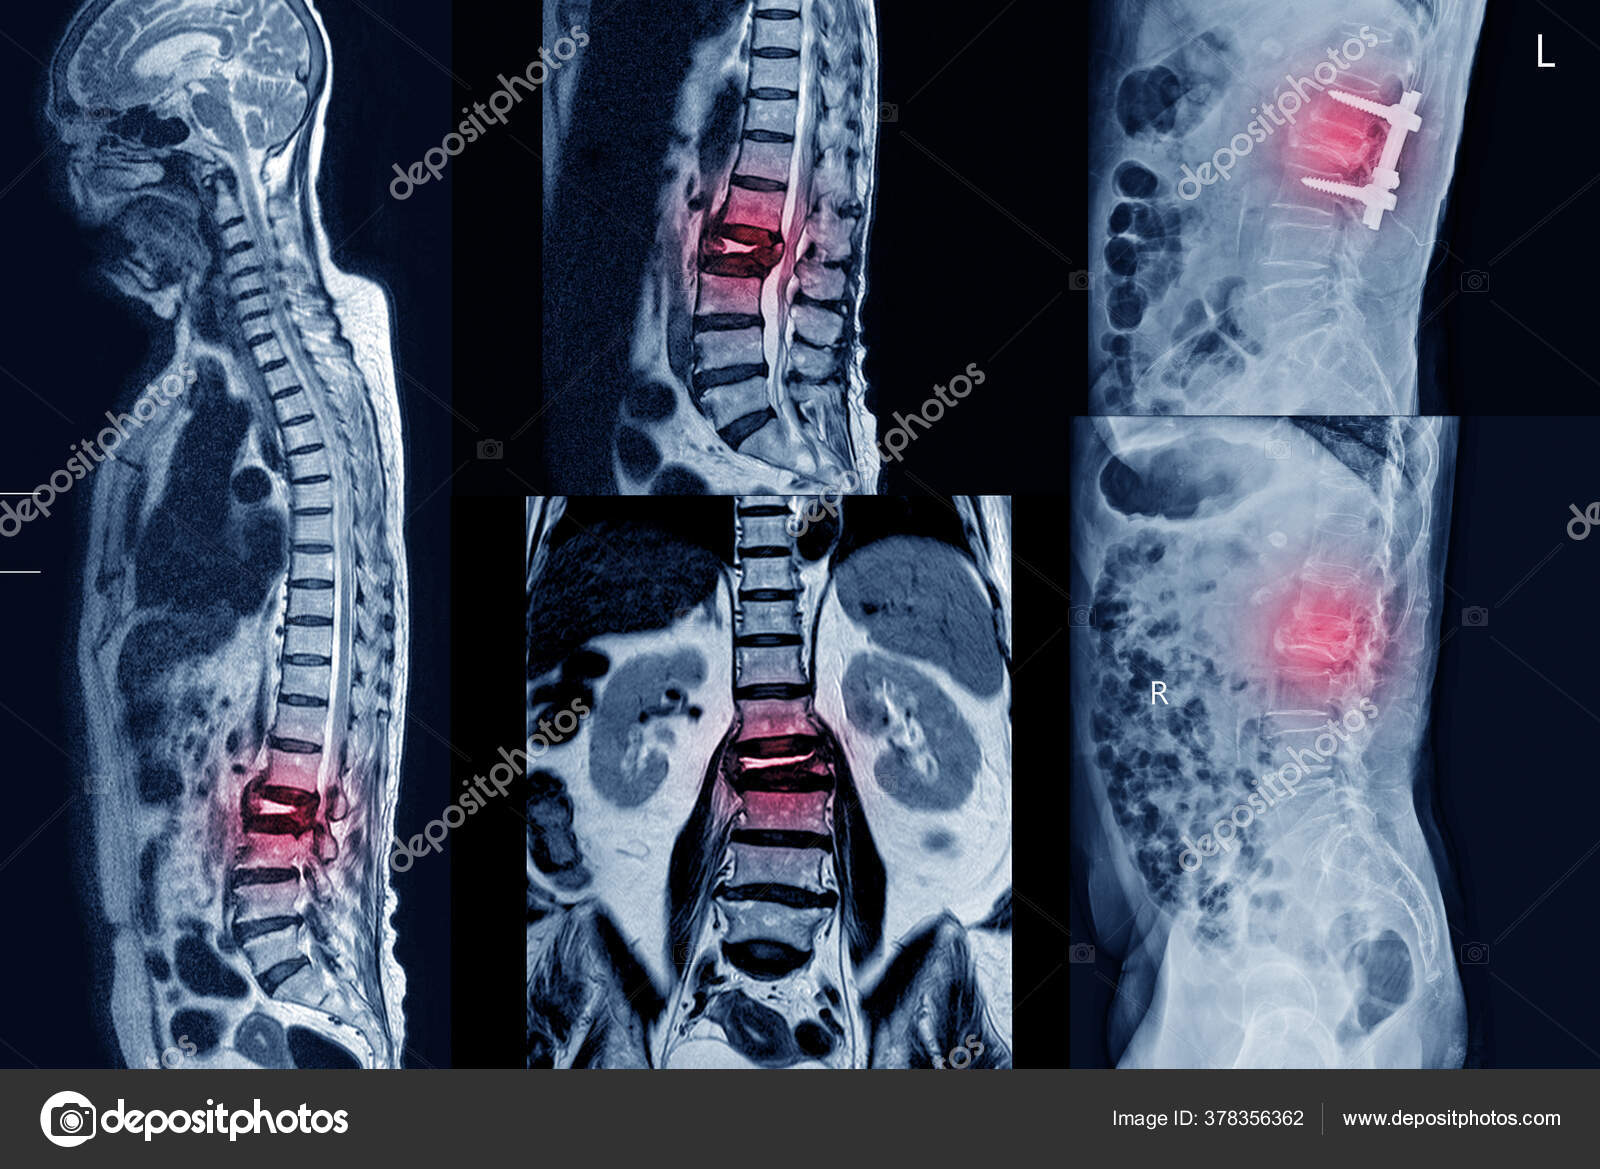

Перед выполнением вертебропластики обязательно проведение предварительного диагностического обследования

Перед процедурой проводят тщательную диагностику, используя методы:

• цифровой рентгенографии,

• рентгеновской компьютерной томографии,

• магниторезонансной томографии,

• сцинтиографии.

Диагностика

Для установления диагноза проводится на начальном этапе проводят рентгенографию позвоночника. Для точного определения локализации и размеров опухоли выполняется тщательная топометрическая подготовка с использованием КТ и МРТ, а также исследование состояния окружающих здоровых тканей.